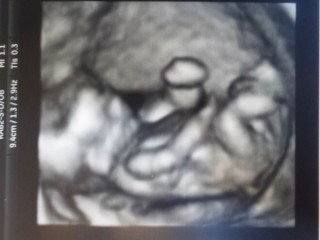

初めての4Dエコー鮮明さにびっくり!指しゃぶりしてかわいいねーって言われました。 もうこんなに似るものなのかと思うくらいパパにそっくりです。。 動画は沢山動いてむにゃむにゃしてて感動でした! 全身が写るのは20wまでと聞いたので、成長が楽しみです!

初めての4Dエコーでした!

立体的に見れてお腹の中に赤ちゃんが

いるんだなぁって実感できました。

次の検診も楽しみです。